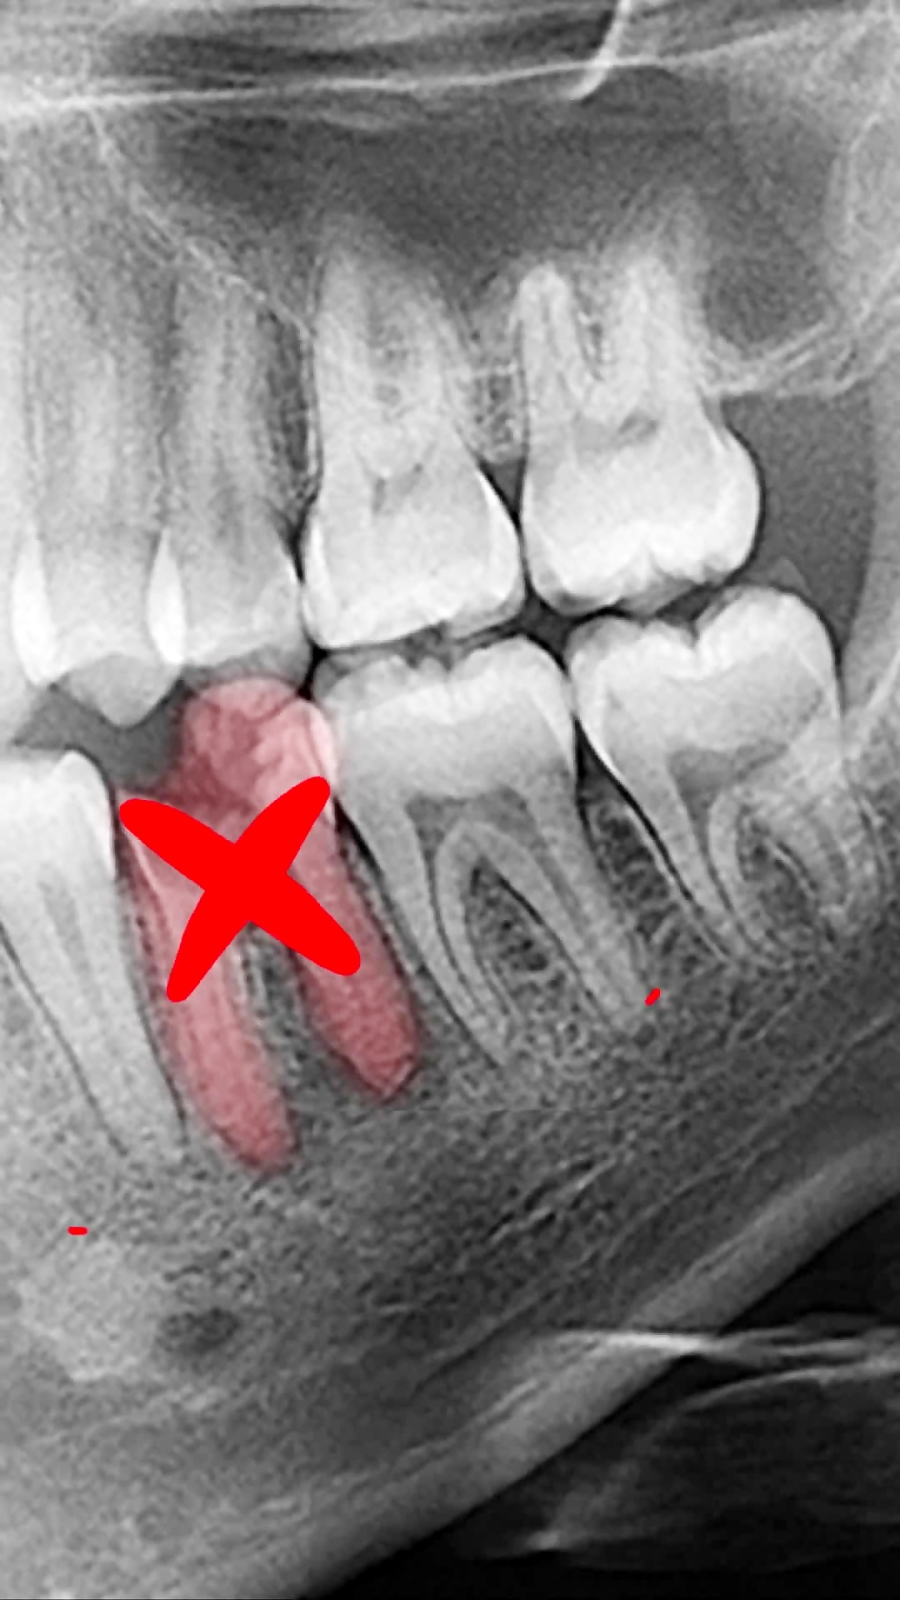

باز کردن فضای ایمپلنت با ارتودنسی | دکتر داودیان

147 بازدید